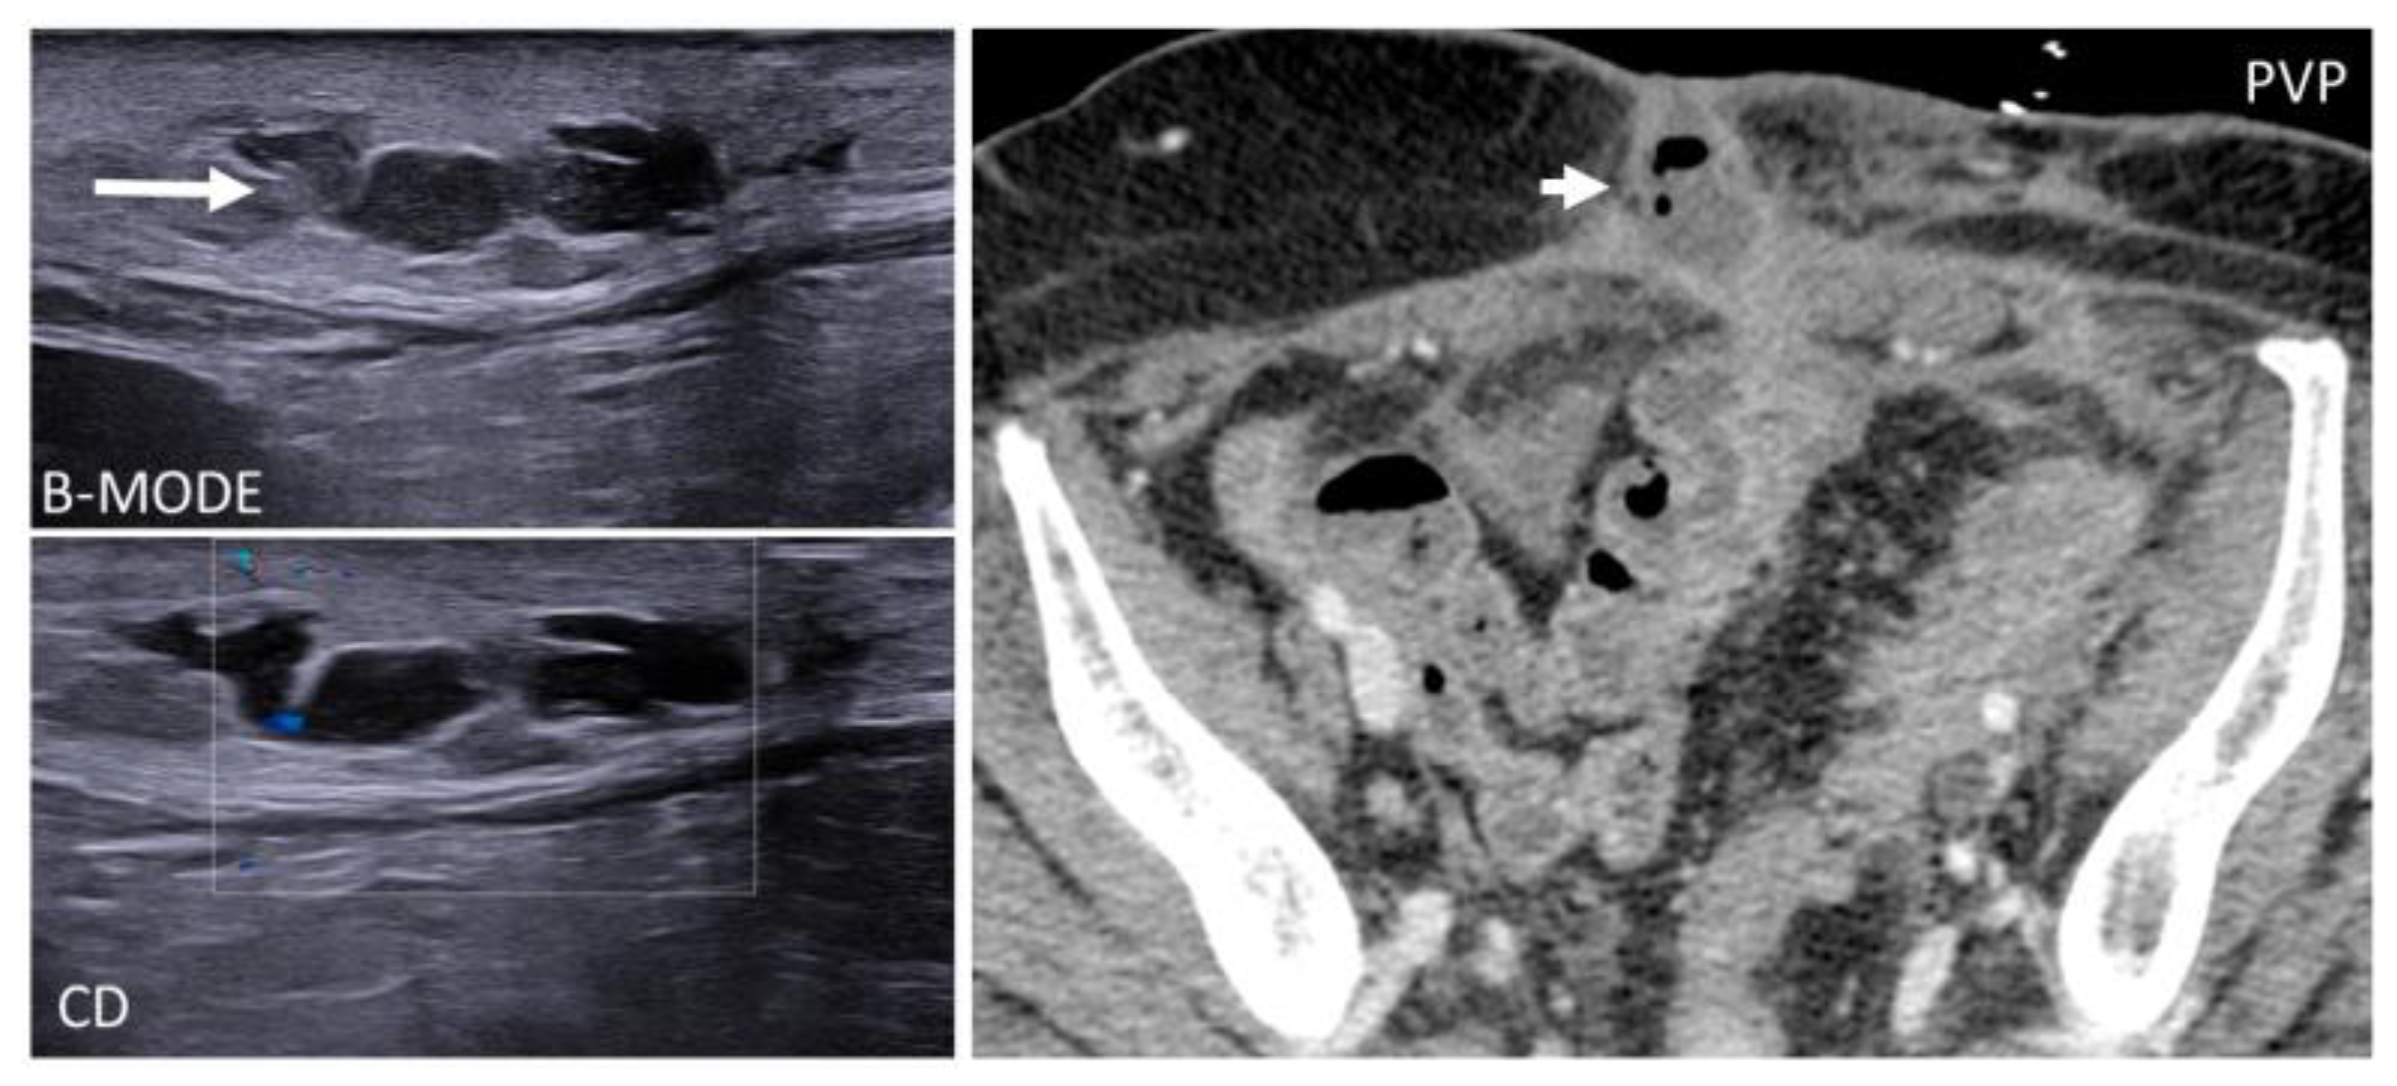

US appearance is non-specific as it shows round or oval-shaped, hypo- to isoechoic solid masses with posterior acoustic enhancement and an incomplete hyperechoic rim [47]. CT and MR will show round lesions with imaging and contrast behavior similar to the spleen. In doubtful cases, heat-denatured blood cell scintigraphy should be considered [46,47] (Figure 16). Splenosis does not require follow-up or pose a risk for degeneration. Evidence shows that there is no need for surgical excision since it represents normal-functioning splenic tissue [47].

Figure 16. A 59-year-old woman who underwent splenectomy some years prior. During a CT scan, new, rounded masses (circles) were found along the peritoneum and the left rectus abdominis muscle. These formations show parenchymal attenuation on CT (pictures 1 and 2) and share the same T2 intensity as the spleen. These lesions were later characterized as splenosis.